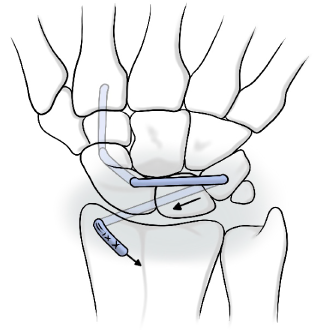

수술적 치료법

봉합술

재건술

수술

• 시기

• 파열된 지 얼마 안되었을 때

• 파열되고 시간이 경과한 후

• 치료방법

• 관절경 또는 절개 하에 봉합

• 힘줄 및 인대의 이식을 통한 재건

• 수술 후 재활

• 수술 후 4~8주 고정

1~2 개월간 재활

3개월이상 재활

인대재건술 1

인대재건술 2

근위 수근열 절제술